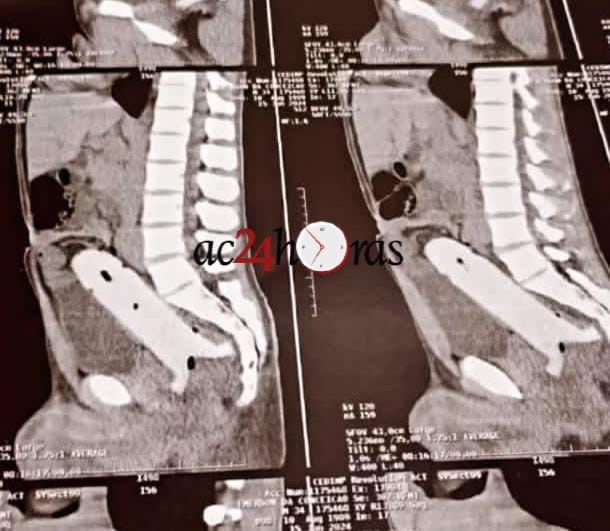

Os paramédicos foram acionados, o colocaram dentro da ambulância e tentaram retirar o objeto do reto. Porém, devido a profundidade, não foi possível removê-lo. O homem foi levado pela ambulância ao pronto-socorro de Rio Branco, onde passou por um procedimento cirúrgico para a retirada do vibrador. O estado de saúde da vítima é estável.